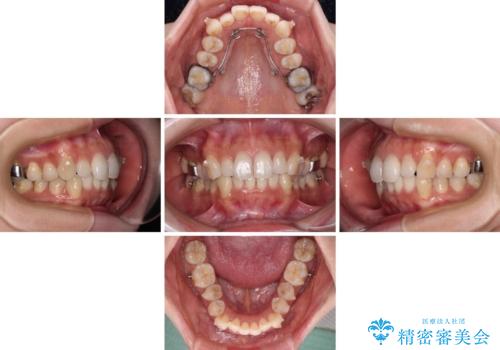

- 2年4ヶ月

歯列としてはインビザラインでもワイヤー矯正でも対応できるものでしたが、奥歯の咬み合わせを見た時に上顎がやや前方にあり、インビザライン単独では時間のかかってしまう可能性があるため、補助装置を治療当初に使用することで、インビザラインによる治療をスムーズに行えるように計画しました。

インビザラインは得意・不得意の差がはっきりとしているため、補助装置やワイヤー装置などをうまく活用することで、治療期間を短縮するとともに、より理想的な仕上がりを達成することができます。